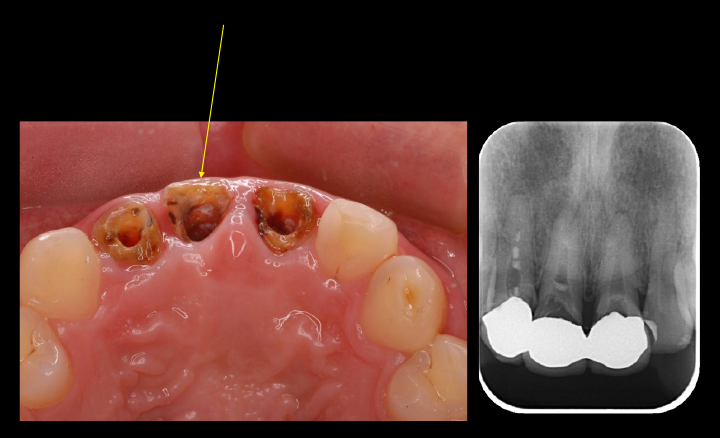

他院にて右上前歯が虫歯で抜歯と診断

他院にて右上の前歯は虫歯と根の先にできた炎症で保存ができないと言われて当院を受診されました。

強く保存を希望されたため、根管治療と矯正治療、歯周形成外科を行い保存を試みることにしました。

根管治療終了時口腔内写真およびレントゲン写真

根管治療終了時のレントゲン写真及び口腔内写真です。右上1番の根尖病巣の縮小がみられるため、保存可能と判断し矯正治療を行うことにしました。